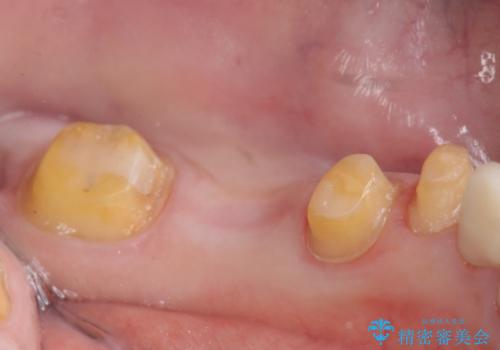

- 左下の銀歯を前の歯に合わせて白くしたいといらっしゃった方の症例です。

前歯部のシェードに合わせ、左下4及び左下567ブリッジをオールセラミッククラウンにて補綴しました。

- オールセラミッククラウン…¥100,000×4、仮歯…¥10,000×4費用は治療当時の料金となります